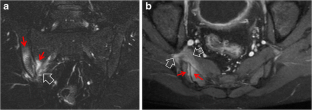

Fig. 1

Fig. 2

Fig. 3

Fig. 4

Fig. 5

Fig. 6